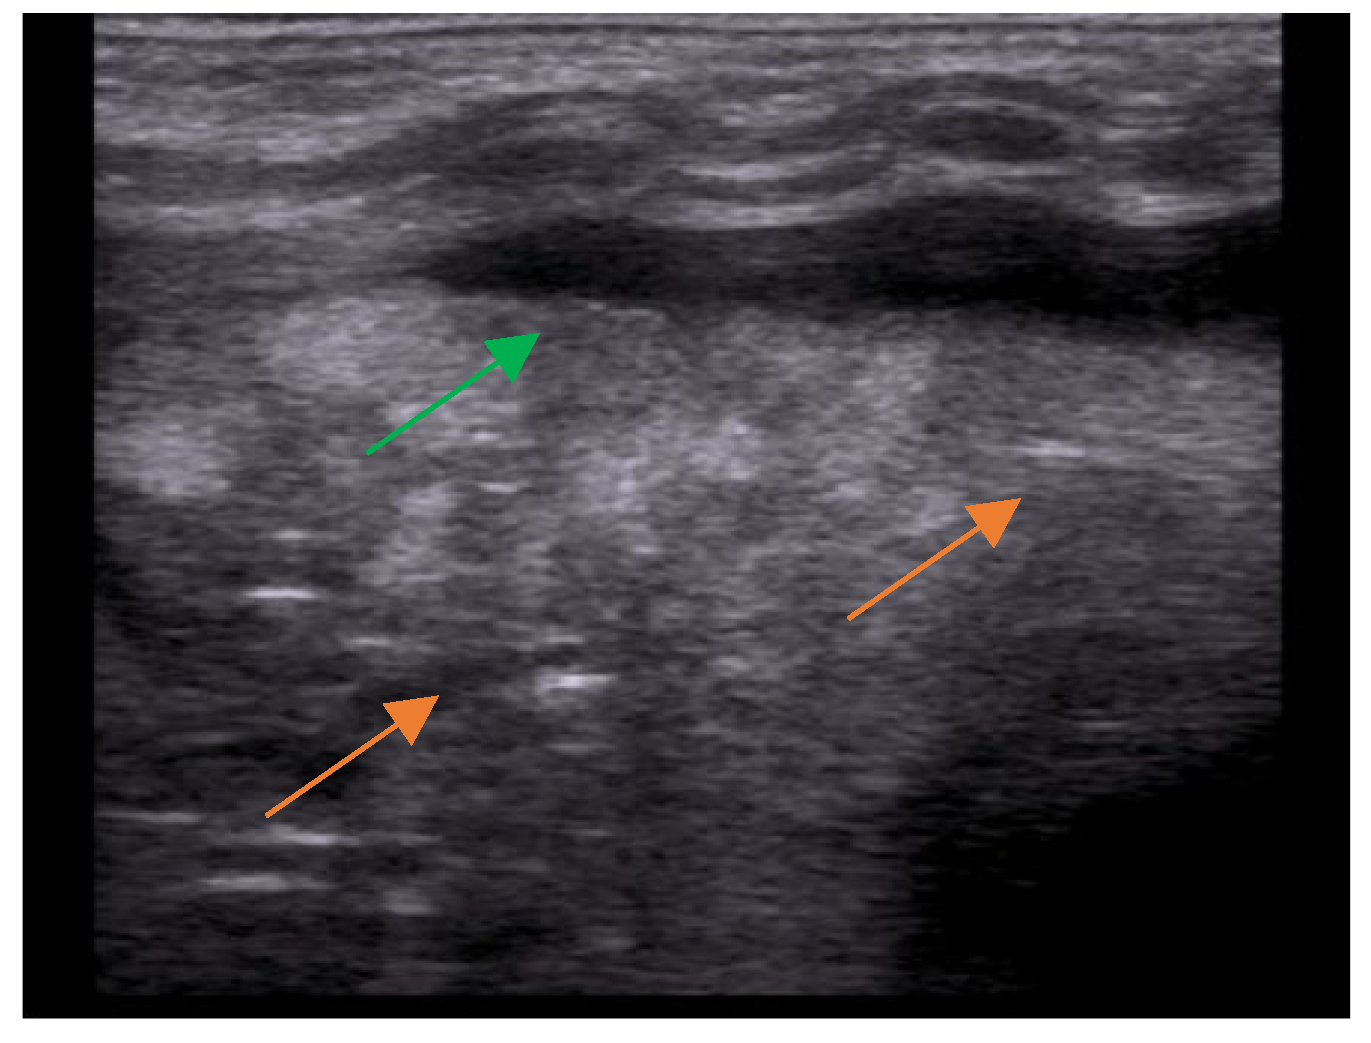

- The main lesion (consolidation): size, whether it is single or multiple, location (monolateral or bilateral). The presence of small subpleural consolidations (<1 cm).

- The presence of a bronchogram and its characteristics (air or fluid), morphology (branched or dot-like), dynamics during breathing (poorly or clearly dynamic); vascular pattern, presence of lung point and pulmonary pulse.

- The presence and type of pleural effusion.